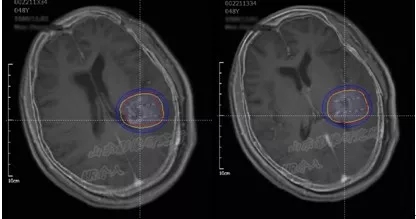

术前TPS计划

术后24小时内MRI/CT图像融合

MR/CT融合图像解决了I125放射性粒子在磁共振图像上显示不清、CT图像病灶轮廓勾画

困难的缺点,达到精准的病灶与粒子的空间分布显示,有利于术后的TPS验证。